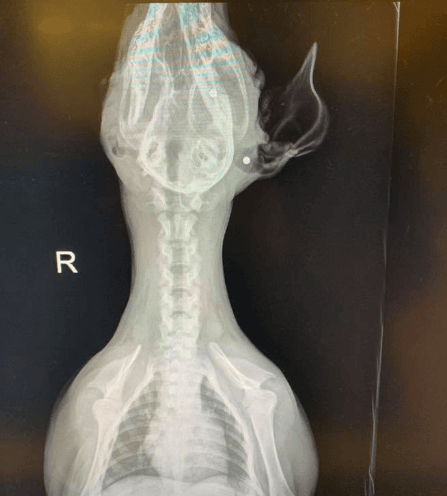

El hombre estuvo 12 días inconsciente. Por la gravedad de la herida, los médicos tuvieron que amputarle la pierna izquierda y lo operaron en nueve ocasiones.

Ahora usa una prótesis de titanio, por lo que volvió a caminar, hacer sus actividades cotidianas y también tiene deseos de volver a la cacería, aunque ya no pueda maniobrar o hacerlo como antes. “No voy a echarle la culpa a la caza, ni a las armas", expresó.